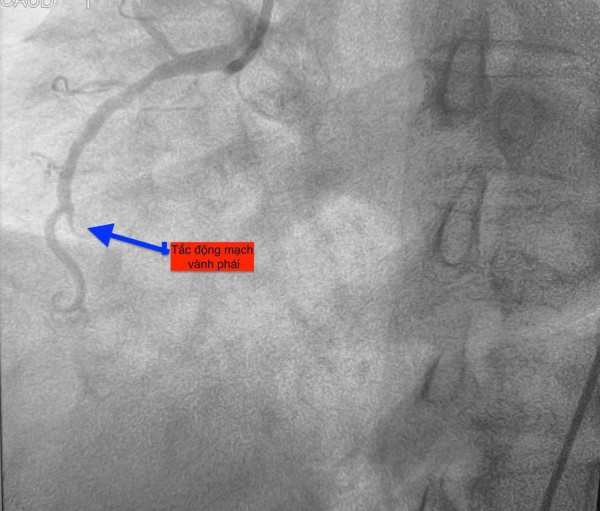

Trường hợp thứ nhất, lúc 0 giờ 34 phút ngày 14.11, nam bệnh nhân 51 tuổi vào bệnh viện vì mệt và khó thở. Chụp mạch vành phát hiện bệnh nhân bị tắc hoàn toàn động mạch vành phải.

Hình ảnh chụp mạch vành cho thấy các bệnh nhân bị tắc mạch máu tim (do mảng xơ vữa, huyết khối) dẫn đến tình trạng thiếu máu cục bộ và nhồi máu cơ tim cấp